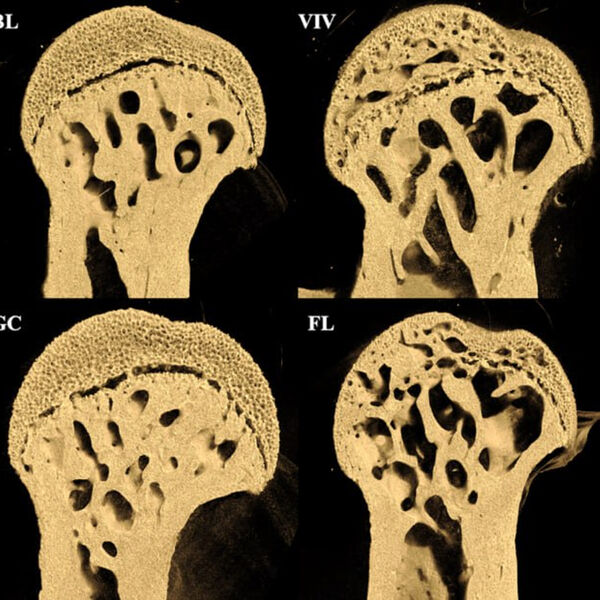

PLOS One: в невесомости у мышей образуются отверстия на концах бедренных костей

Эксперимент продолжительностью 37 дней показал, что у мышей в космосе значительно пострадали бедренные кости, в то время как поясничный отдел позвоночника остался практически неповрежденным.

Особенно заметные повреждения — крупные отверстия — обнаружились на концах бедренных костей в местах соединения с тазобедренным и коленным суставами.